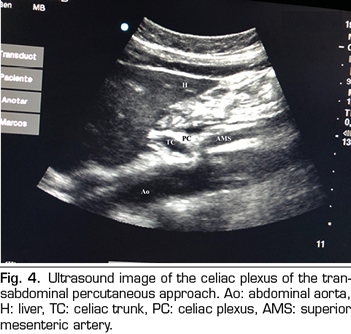

Figure 3